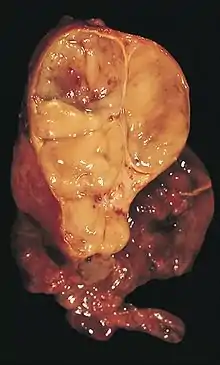

An encapsulated thymoma (mixed lymphocytic and epithelial type) | |